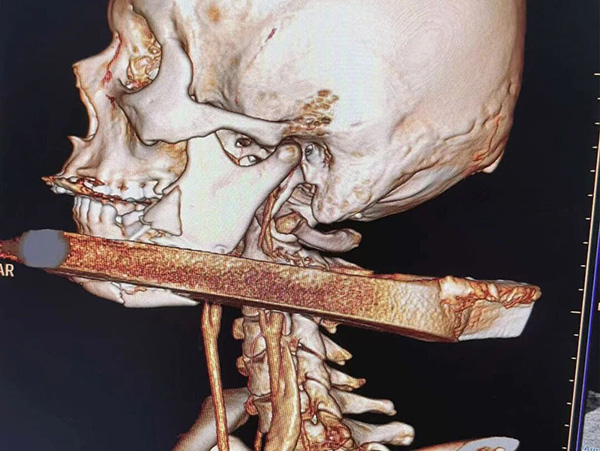

一根长度约1米、直径约3厘米的铁撬棍从颈后穿入,紧贴颈椎与颈总动脉之间的狭窄缝隙,径直从左侧面部穿出,锋利棱边紧贴维系生命的颈总动脉——这并非影视剧中虚构的惊险桥段,而是发生在现实生活中、命悬一线的真实危机。面对罕见颈面部贯通伤病例,齐齐哈尔市第一医院迅速启动紧急救治预案,集结多学科精锐力量,以分秒必争的救援速度、毫厘不差的手术精准度,完成了一场跨越地域、与死神赛跑的生命接力。

3月9日,王先生在田间劳作时,意外突然降临。一根粗大且带有锋利棱角的金属撬棍,瞬间从其颈椎后侧穿入,穿透颈部多层软组织,经颈椎与颈总动脉之间的狭小间隙从左侧颏部穿出。巨大的冲击力将王先生左侧下颌骨砸至粉碎,口腔内软组织大面积严重撕裂,颈部创口鲜血喷涌不止,生命体征瞬间告急。

当手术区域被逐层打开后,眼前的景象让见惯了危重伤情的医护人员也不禁心头一紧。粗大的撬棍死死卡在颈面部狭窄空间内,周围组织严重肿胀、撕裂,下颌骨碎片散落其间;更为凶险的是,带有锋利棱角的撬棍与颈总动脉紧紧贴合,仅隔一层薄如蝉翼的软组织,稍有牵拉、触碰,就可能划破这根维系生命的大动脉,导致患者在几分钟内死于致命性大出血,没有任何挽回余地。

手术最凶险、最艰难的环节,无疑是异物取出与血管神经保护。邱澄宇与刘强屏气凝神、配合默契,逐层解剖被挤压损伤的软组织,一点点剥离粘连。随后,邱澄宇用止血带精准固定血管后,目光死死锁定颈总动脉,观察血管的细微变化;刘强则全程稳稳把控撬棍位置,将40余公分长的撬棍从“生命禁区”缓缓取出。当撬棍被完全取出的那一刻,手术室里所有人都长舒一口气,而两位主任的双手,因长时间保持固定姿势早已僵硬,鬓角与额头的汗水也浸透了手术帽。